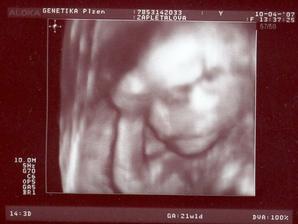

Tomášek se narodil přesně 3 týdny před termínem v Plzni na Slovanech 30.7.2007 Měřil 50 cm a vážil 2900g